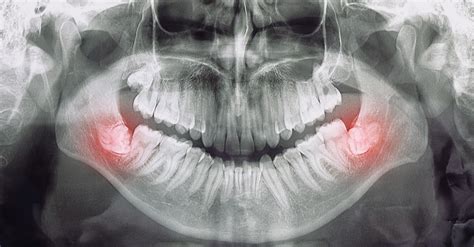

Las muelas del juicio, también conocidas como terceros molares o cordales, suelen aparecer en la boca entre los 17 y 25 años, edad en la que se “tiene juicio” o se “es más cuerdo”. Sin embargo, la edad óptima para la extracción dependerá de la evaluación del especialista y cada caso concreto ya que no existen dos bocas iguales.

Muela del juicio retenida.

En ocasiones estos molares se desarrollan bien y brotan sin problemas. Pero hay casos en los que no tienen suficiente espacio, esto causa que queden retenidas o salgan solo de forma parcial. En este último caso puede ocurrir que crezca en ángulo hacia el segundo molar o hacia atrás; o que esté derecha, pero atrapada en el maxilar.